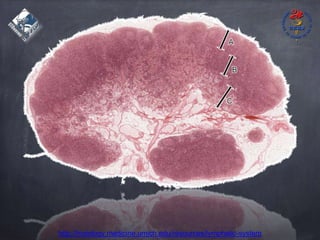

Linfonodomegalia

http://histology.medicine.umich.edu/resources/lymphatic-system

Junqueira, 12ªed